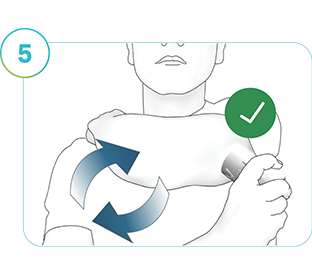

Steg 5

Applicera en ny sensor. Varje gång du byter sensor ska du välja en ny plats på överarmens baksida så att det förra applikationsstället kan läka ordentligt. Vi rekommenderar att du växlar mellan vänster och höger arm för att ge applikationsställena lämplig läkningstid.